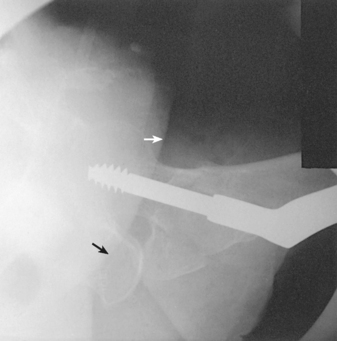

CLEMENTS-NAKAYAMA MODIFICATION

When the patient has bilateral hip fractures, bilateral hip arthroplasty (plastic surgery of the hip joints), or limitation of movement of the unaffected leg, the Danelius-Miller method cannot be used. Clements and Nakayama1 described a modification using a 15-degree posterior angulation of the central ray (Fig. 7-38).

• For this position, do not rotate the lower limb internally. Instead, the limb remains in a neutral or slightly externally rotated position.

• Support a grid IR on the Bucky tray so that its lower margin is below the patient. Position the grid so that the lines run parallel with the floor.

• Adjust the grid parallel to the axis of the femoral neck, and tilt its top back 15 degrees.

• Directed 15 degrees posteriorly and aligned perpendicular to the femoral neck and grid IR (Fig. 7-39)

Structures shown: This leg position shows a lateral hip image because the central ray is angled 15 degrees posterior instead of the toes being medially rotated. The resulting image shows the acetabulum and the proximal femur including the head, neck, and trochanters in lateral profile. The Clements-Nakayama modification (Fig. 7-40) can be compared with the Danelius-Miller approach described previously (Fig. 7-41).